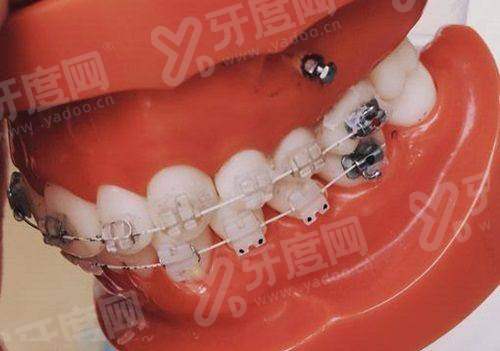

(三)西捷美牙冠临床适用人群与修复成效

1、对于前牙美学修复,西捷美全瓷冠的透光性和色泽层次感表现优异,能够良好地模拟天然牙的质感,避免“假白”现象。

2、在后牙咀嚼功能修复上,其材料强度足以应对日常饮食需求,适合大多数单颗缺失或根管治疗后的牙齿保护。

(三)加工精度与后期维护要点

1、优点明显:依托数字化扫描与切削,西捷美牙冠的边缘密合度特别高,能有效减少食物残渣堆积,降低继发龋齿的发生概率。